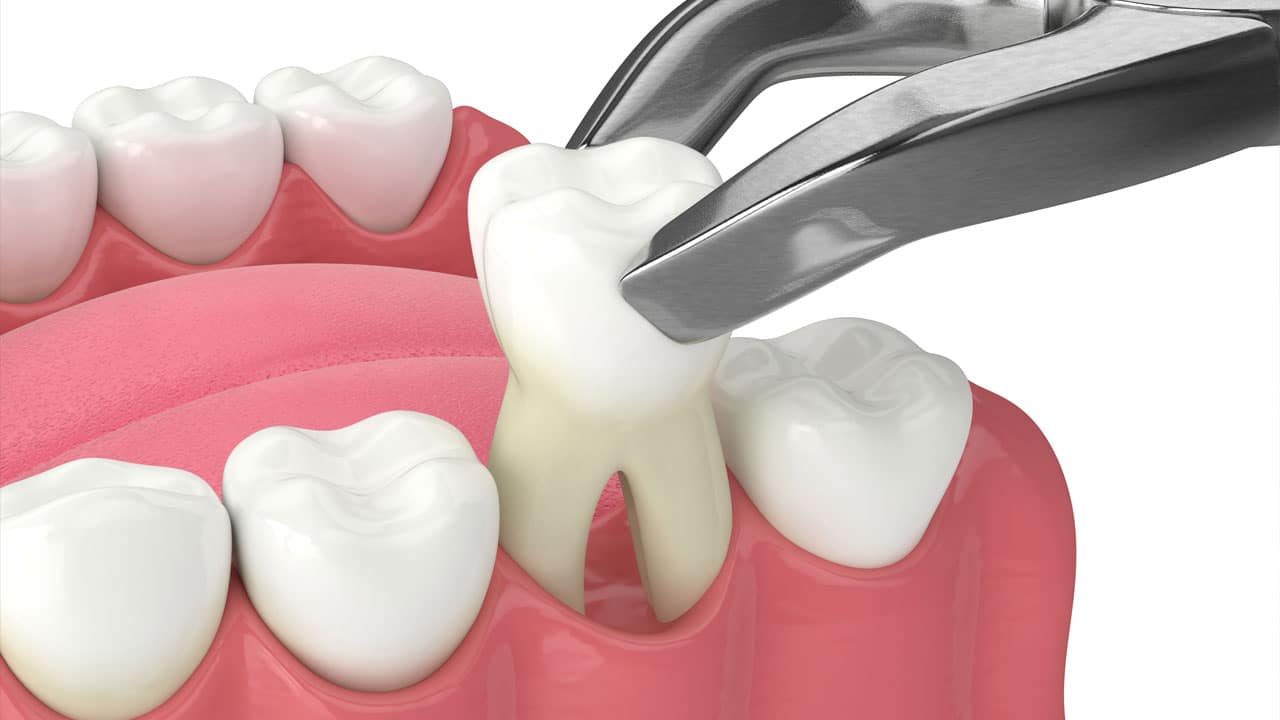

Treatment at our clinic is offered on a private basis and also to PRSI-qualified patients. Services include all routine dental treatment (examinations, cleanings, fillings etc.), cosmetic dentistry such as teeth whitening, bonding and porcelain veneers as well as more advanced procedures including the provision of crowns and bridges and dental implants.

We also provide specialist prosthodontic services here at Shelbourne so we can cater for those patients requiring extensive dental treatment such as full mouth reconstructions, severe wear cases and advanced cosmetic dentistry.